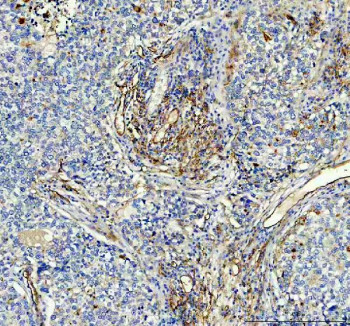

Adding 0.2 ml of distilled water will yield a concentration of 500 ug/ml. ACE antibody detects Angiotensin I converting enzyme, a zinc-dependent peptidase that plays a pivotal role in blood pressure regulation and electrolyte balance. The UniProt recommended name is Angiotensin I converting enzyme (ACE). This membrane-bound enzyme catalyzes the conversion of angiotensin I to the potent vasoconstrictor angiotensin II and degrades bradykinin, thereby modulating vascular tone and fluid homeostasis.Functionally, ACE antibody identifies a 1,306-amino-acid type I membrane glycoprotein composed of two homologous catalytic domains (N- and C-domains) and a short cytoplasmic tail. ACE is expressed in endothelial cells, epithelial cells, and kidney proximal tubules, where it acts as a key enzyme of the renin-angiotensin system (RAS). By generating angiotensin II, ACE promotes vasoconstriction, sodium retention, and aldosterone secretion, contributing to blood pressure regulation.The ACE gene is located on chromosome 17q23.3 and encodes multiple isoforms, including somatic ACE and testis-specific ACE (tACE). Somatic ACE is primarily found on the luminal surface of endothelial cells in lungs, heart, and kidneys, whereas tACE functions in sperm maturation and fertility. ACE expression is regulated by inflammatory cytokines, hormonal signaling, and mechanical stress on vascular endothelium.Clinically, dysregulation of ACE activity is linked to hypertension, heart failure, diabetic nephropathy, and atherosclerosis. ACE inhibitors, which block enzyme activity, are among the most effective therapeutics for cardiovascular disease management. Beyond cardiovascular roles, ACE contributes to immune function by degrading inflammatory peptides and influencing hematopoietic stem cell mobilization. Elevated ACE levels are also diagnostic for sarcoidosis and other granulomatous disorders.ACE antibody is widely used in cardiovascular, renal, and molecular physiology research. It is suitable for immunohistochemistry, western blotting, and flow cytometry to detect ACE expression and distribution in tissues. This antibody supports studies of vascular biology, RAS signaling, and peptide metabolism. In clinical and translational settings, ACE serves as a biomarker for endothelial activation and inflammatory vascular disease.Structurally, ACE consists of two catalytic domains containing zinc-binding motifs (HEMGH sequence) that coordinate enzymatic hydrolysis of peptide bonds. Its extracellular domain is heavily glycosylated, conferring stability and resistance to proteolysis. NSJ Bioreagents provides ACE antibody reagents validated for use in cardiovascular physiology, renin-angiotensin system, and molecular enzyme research.

| Application: | WB, IHC, ELISA |